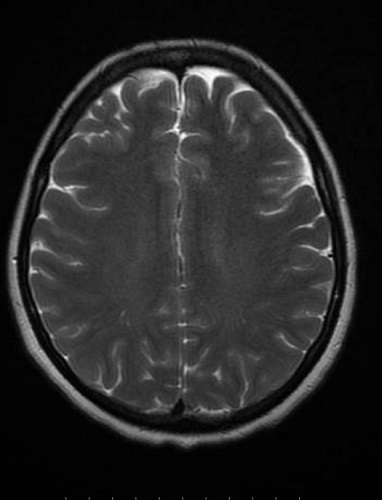

ام آر آی مغز نوعی آزمایش تصویربرداری بدون درد است که با استفاده از آن تصاویر واضحی از ساختارهای سر ارائه می شود و پزشک معالج این نوع تصویر برداری را برای ارزیابی تشخیص و نظارت بر بیماری های مختلف که به مغز مربوط می شوند تجویز می کند. در دستگاه ام آر آی از یک آهنربای بزرگ ، امواج رادیویی و کامپیوتر برای تولید تصاویر استفاده می شود و بر خلاف سایر دستگاه های تصویر برداری ، اشعه یونیزان در آن نقشی ندارد. امروزه ام آر آی مغز از سایر روش های تصویر برداری مانند سی تی اسکن ، رادیولوژی با اشعه ایکس حساس تر بوده و تصاویر دقیق تری را از مغز ارائه می دهد.

ام آر آی مغز یک تکنیک تصویر برداری غیر تهاجمی است که بافت نرم مغز ، مخ و مخچه ، عروق مغزی و استخوان کاسه سر و دیگر جزئیات مغز را بخوبی نشان می دهد و برای ایجاد تصاویر از میدان مغناطیسی قوی و فرکانس رادیویی استفاده می کند. در برخی مواقع پزشک ام آر آی مغز با کنتراست تزریقی را برای بیمار تجویز می کند که در آن از ماده حاجب استفاده می شود و ماده کنتراست تزریقی اغلب گادولینیوم است که نوعی فلز خاکی کم یاب بوده و در صورت حضور در بدن باعث تغییر خواص مغناطیسی مولکولهای آب مجاور می شود و کیفیت تصاویر را افزایش می دهد.

ماهیت ام آر آی سر و مغز یکی است و در اکثر مواقع با هم انجام می شوند با این تفاوت که در ام آر آی سر ، ساختار های دیگری همچون استخوان های سر و صورت ، رگ های خونی ، اعصاب و ... قابل مشاهده است اما در ام آر آی مغز همانطور که از نامش پیداست ، تنها قسمت مغز مورد بررسی قرار می گیرد.

ام آر آی سر تمامی قسمت های داخلی سر از جمله مغز ، رگ های خونی متصل به مغز ، استخوان ها و جمجمه ، ساختار گوش داخلی ، چشم ها و بافت های اطراف آن ، اعصاب بینایی و سایر عصب های درون سر ، ساختار های مربوط به جمجمه مانند ماهیچه و بافت های همبند و ... را به خوبی نشان می دهد. همچنین ام آر آی سر به خوبی توده های غیر طبیعی ، وجود مایع ، التهاب و تورم ، خونریزی مغزی و هرگونه بیماری مربوط به مغز را به خوبی نشان می دهد.